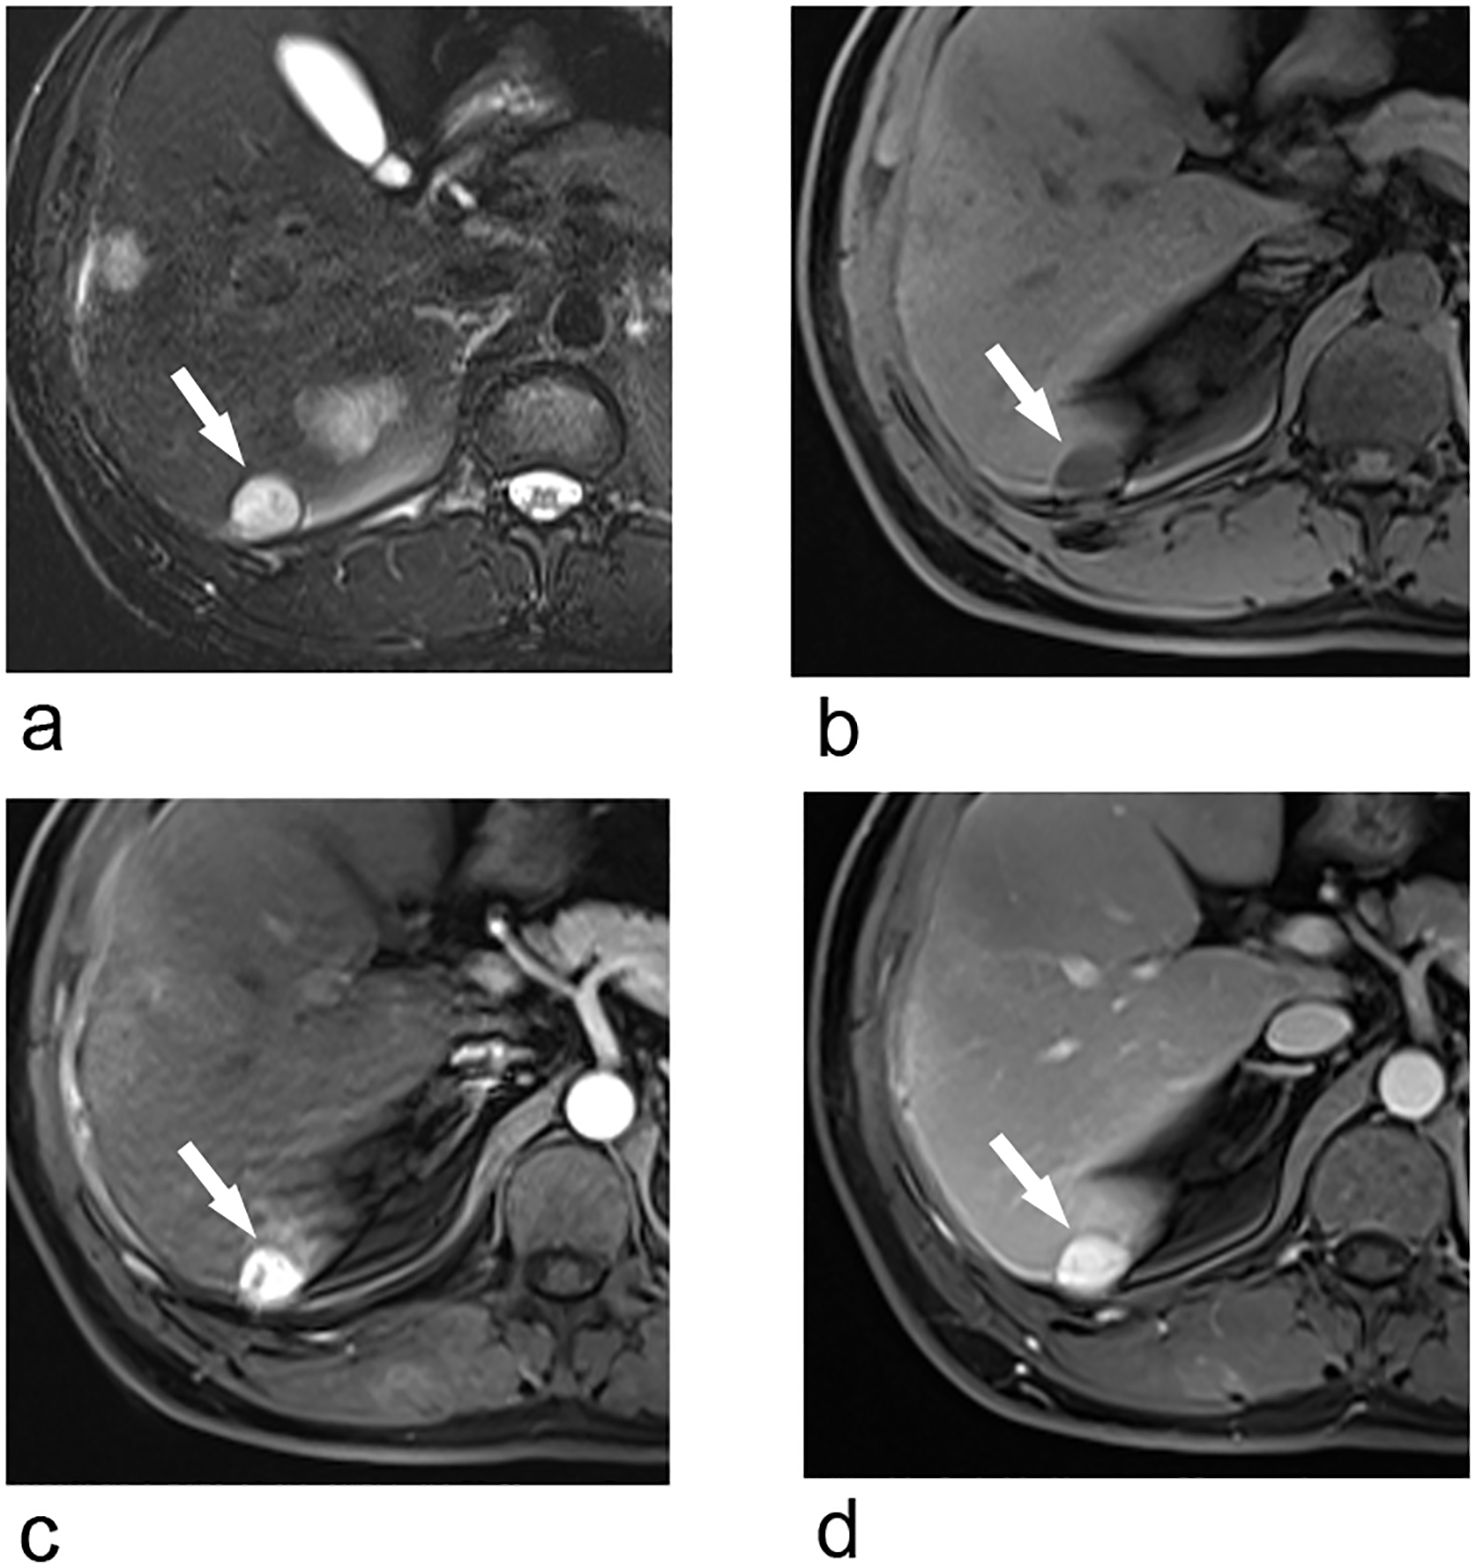

Upper abdominal MRI (3.0T, Magnetom Verio, Siemens, Germany) was subsequently performed. The large liver mass was heterogeneous on MR images, with hypointense on T1-weighted images and hyperintense on T2-weighted images. There were multi-lobulated, cystic areas within the mass. After injection of gadoxetic acid (Gd-BOPTA, MultiHance, Shanghai Bracco Sine Pharmaceutical, China), the mass showed inhomogeneous hyperintense in arterial phase and revealed prolonged enhancement in the portal venous phase and delayed phase (3 min). In hepatobiliary phase, the mass was hypointense with the cystic areas hyperintense. In addition, the liver capsule and the adjacent peritoneum also showed obvious enhancement (Figure 2). The nodule was hypointense on T1-weighted imaging and hyperintense on T2-weighted imaging. It revealed marked enhancement in arterial phase, and showed prolonged enhancement in portal venous phase and delayed phase (Figure 3).

Figure 3. Transverse breath-hold turbo spin-echo T2-weighted image (repetition time msec/echo time msec, 3000/104) (a) and fat-suppressed T1-weighted volume interpolated body examination (VIBE) image (repetition time msec/echo time msec, 3.92/1.39) (b) shows a well-circumscribed liver nodule. Transverse arterial phase (c) and portal venous phase (d) show marked enhancement of the nodule.